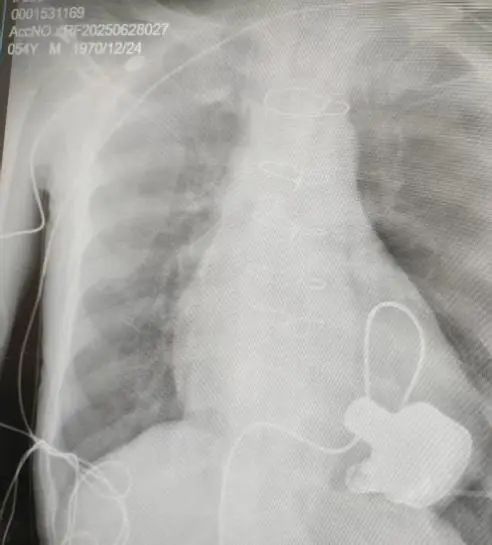

術(shù)后影像